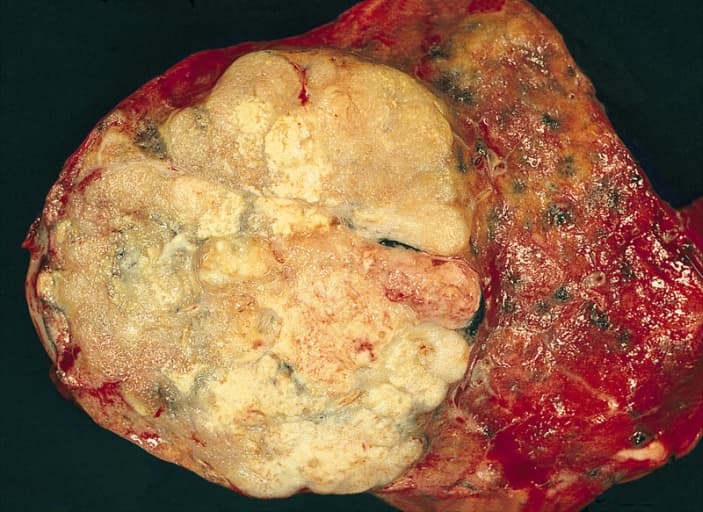

Adenocarcinoma of the lung is the most common type of lung cancer, and like other forms of lung cancer, it is characterized by distinct cellular and molecular features. It is classified as one of several non-small cell lung cancers (NSCLC), to distinguish it from small cell lung cancer which has a different behavior and prognosis. Lung adenocarcinoma is further classified into several subtypes and variants. The signs and symptoms of this specific type of lung cancer are similar to other forms of lung cancer, and patients most commonly complain of persistent cough and shortness of breath. Adenocarcinoma is more common in patients with a history of cigarette smoking, and is the most common form of lung cancer in younger women and Asian populations. The pathophysiology of adenocarcinoma is complicated, but generally follows a histologic progression from cells found in healthy lungs to distinctly dysmorphic, or irregular cells. There are several distinct molecular and genetic pathways that contribute to this progression. Like many lung cancers, adenocarcinoma of the lung is often advanced by the time of diagnosis. Once a lesion or tumor is identified with various imaging modalities, such as computed tomography (CT) or X-ray, a biopsy is required to confirm the diagnosis. Treatment of this lung cancer is based upon the specific subtype and the extent of spread from the primary tumor. Surgical resection, chemotherapy, radiotherapy, targeted therapy and immunotherapy are used in attempt to eradicate the cancerous cells based upon these factors. The majority of patients who are diagnosed with lung cancer usually present with locally advanced or metastatic disease. Only about one third of patients have stage I disease when diagnosed. The symptoms that the patient exhibits usually reflect the extent of the cancer's spread. Lung cancers that are discovered early may cause symptoms localized to the respiratory system. However, lung cancer that is advanced will cause patients to experience additional signs and symptoms secondary to the cancer spreading to other organ systems.